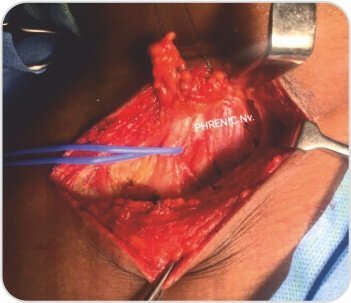

মূল্যায়নে তার ডান সম্পূর্ণ সার্ভিকাল রিব সহ ধমনী থোরাসিক আউটলেট সিন্ড্রোম পাওয়া গেছে। তাকে প্রাথমিকভাবে অ্যান্টিকোঅ্যাগুলেশন দিয়ে পরিচালিত করা হয়েছিল এবং পরে থোরাসিক আউটলেট ডিকম্প্রেশনের জন্য নেওয়া হয়েছিল। ইন্ট্রাঅপারেটিভভাবে রোগীর স্কেলিন পেশী হাইপারট্রফি এবং একটি সম্পূর্ণ জরায়ুর পাঁজর একটি বিস্তৃত প্রথম পাঁজরের সাথে মিশে গেছে যা সাবক্ল্যাভিয়ান ধমনী সংকোচন ঘটায়। ডিকম্প্রেশন পদ্ধতি অনুসরণ করে রোগীর একটি সফল ফলাফল ছিল।

জরায়ুর মুখ এবং প্রথম পাঁজর কাটা